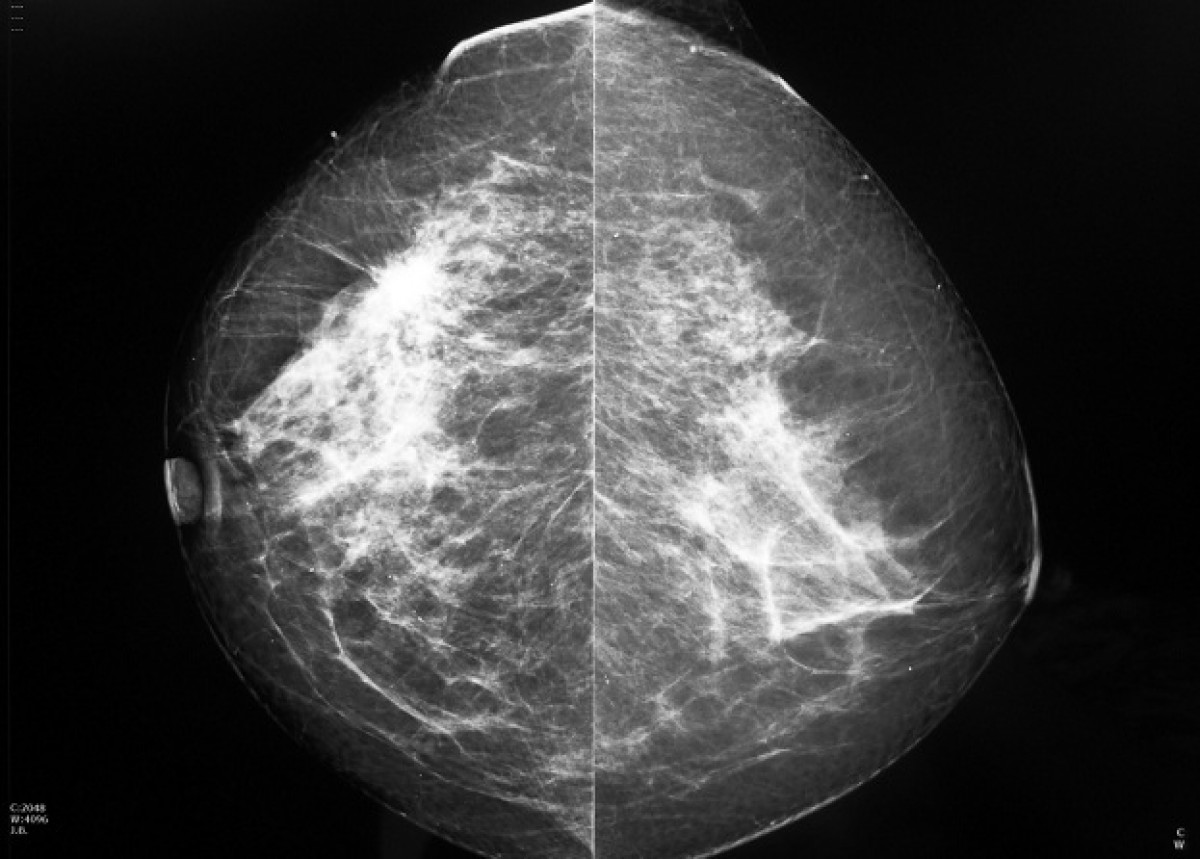

Imagen de una mamografía.